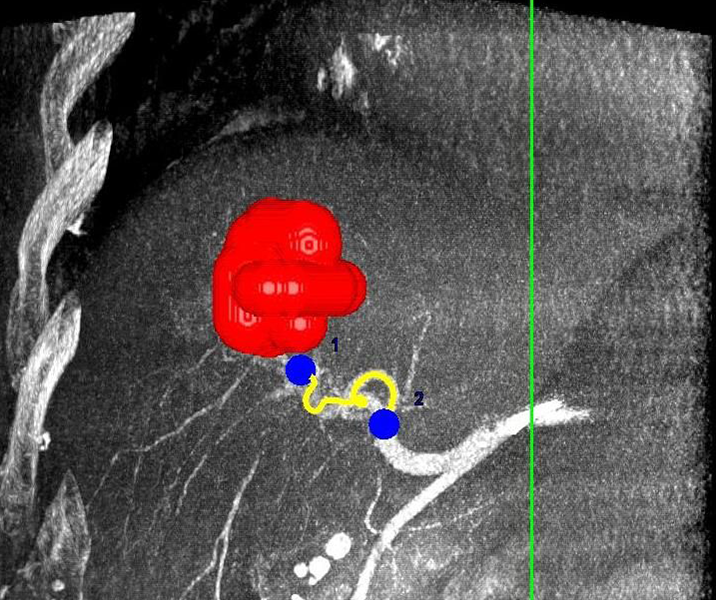

Abbildung: Bei diesem Patienten wurde ein im Röntgen nur schlecht sichtbarer Knochentumor vor der Operation unter MRT-Kontrolle mit kleinen röntgendichten Spiralen („Coils“) markiert. Damit hat der Operateur eine optimale Darstellung des Tumorbereichs bzw. der Tumorgrenzen und kann gezielter, schonender und effektiver operieren.